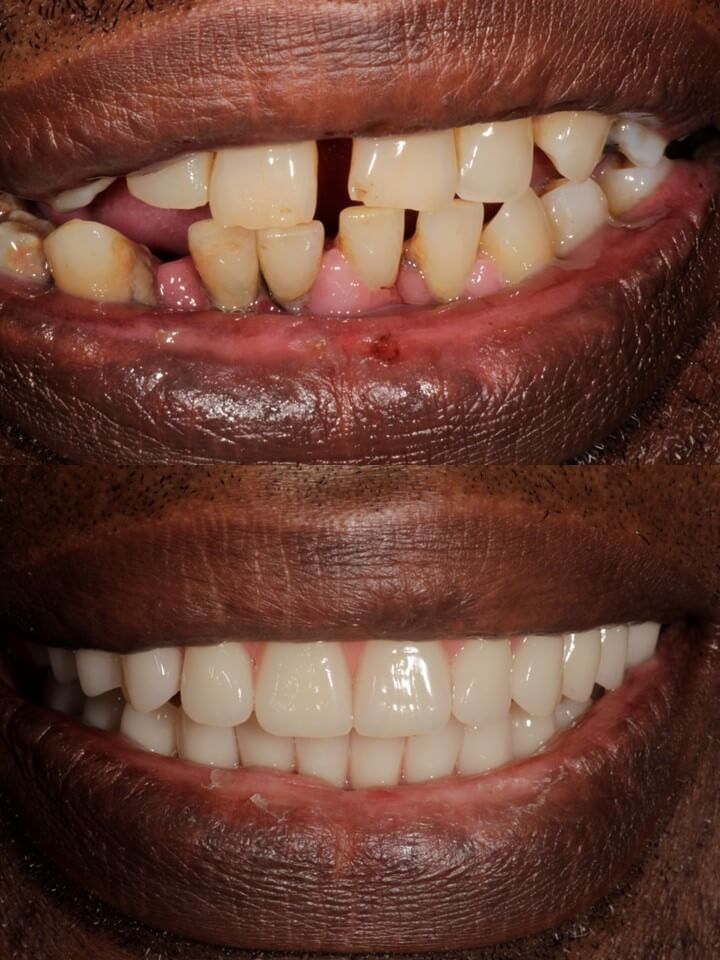

There is no better-fixed tooth replacement solution than a dental implant.

There is no better denture-based treatment than implant-retained dentures

This premium implant treatment provides outstanding chewing strength and a stunningly natural smile. Implant-retained dentures are bespoke dentures that are secured with synthetic replacement tooth roots, AKA dental implants.

All-on-4 ‘Smile in a Day’ implant treatment is the fast-track way to a brand new smile.

Live, laugh and feel confident again with your new bespoke fixed implant bridge. The All-on-4 implant concept involves retaining a fixed bridge in place of dental implants. This provides unparalleled strength and chewing function when compared with removable appliances such as dentures.